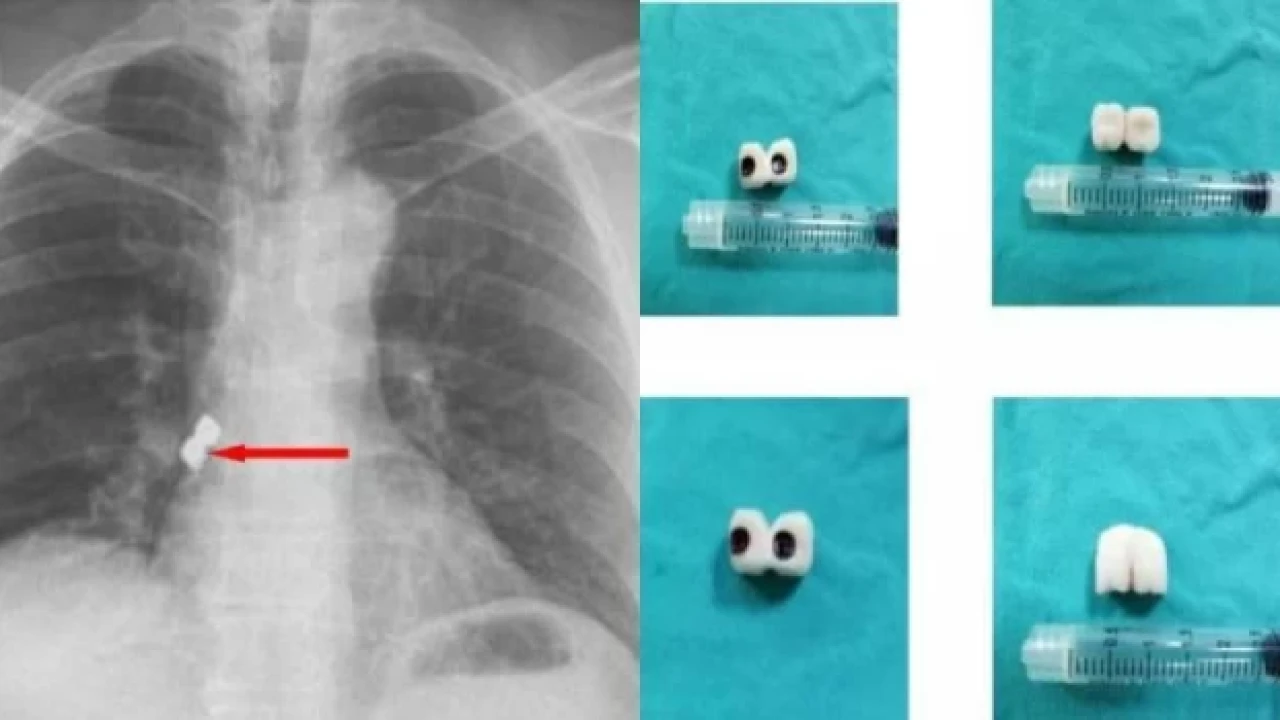

Afyonkarahisar’da, diş tedavisi gören bir şahsın soluk borusuna 2 implant kaçtı. İmplantlar, hastanın akciğer girişinden çıkarıldı.

Afyonkarahisar’da, bir şahsın diş tedavisi sırasında soluk borusuna kaçan iki implant başarıyla alındı.

Belçika’da yaşayan 56 yaşındaki Demet Kaplan, geldiği Emirdağ ilçesinde diş tedavisi için bir kliniğe gitti.

Operasyon sırasında birbirine yapışık olan 2 implant hastanın dişinden düştü.

Kaplan, yutkununca implantlar soluk borusuna kaçarak burayı tıkadı.

Nefes almakta zorlanan Kaplan, Emirdağ Devlet Hastanesi’nde yapılan ilk müdahalenin ardından Afyonkarahisar’da başka bir hastaneye sevk edildi.

İmplantlar, Kaplan’ın akciğer girişinden çıkarıldı.